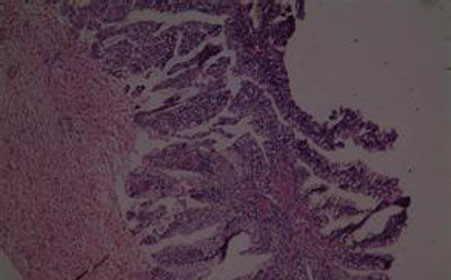

宫颈息肉是妇科的一种常见病,好发于30-50岁的妇女。该病主要是由于慢性炎症的长期刺激,促使宫颈管局部粘膜过度增生,加上子宫有排除异物的倾向,使增生的粘膜逐渐自基底部向宫颈外口突出而形成息肉。息肉多属于良性,但有时也可能是子宫颈的一部分,故须特别注意。